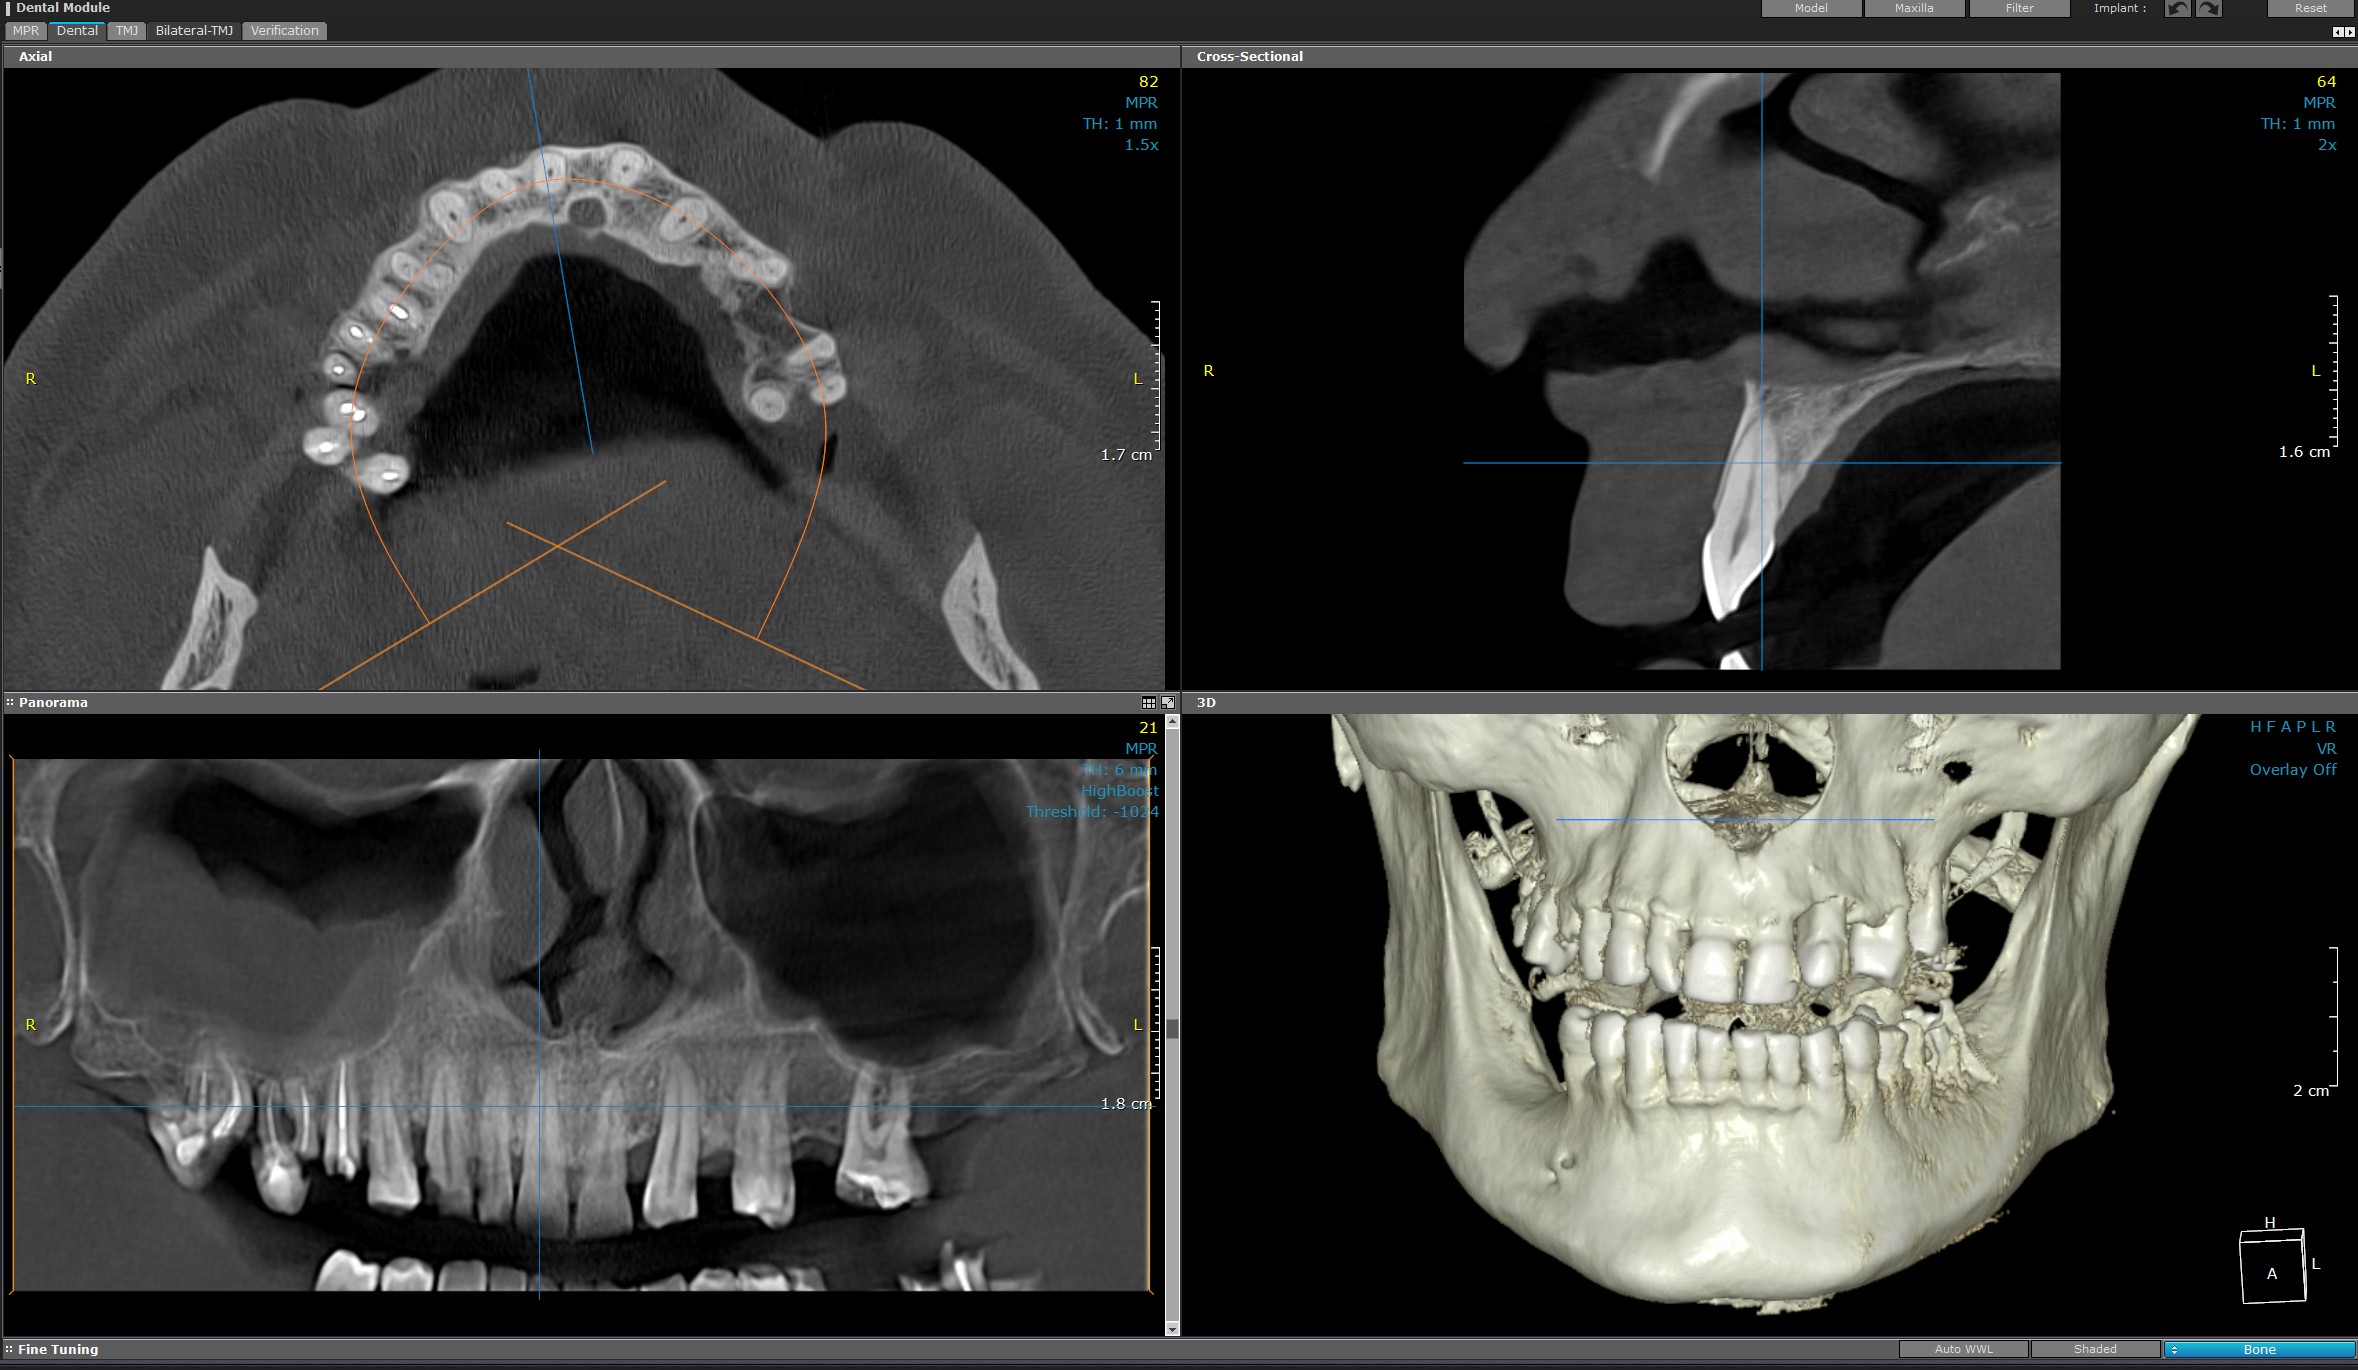

CT Endo (Endodontic)

CT Endo are la bază o tehnologie avansată utilizată de către medicii stomatologi de specialitate pentru diagnosticarea și tratamentul canalului radicular.

Aparatul furnizează imagini detaliate și precise ale dinților și a structurilor radiculare.

Prin imagini tridimensionale, CT-ul endodontic permite medicilor să observe în detaliu canalul radicular, vârfurile radiculare și structurile adiacente, facilitând identificarea infecțiilor, leziunilor, fracturilor sau a altor anomalii ale dinților.

Investigația radiologică contribuie la planificarea tratamentului endodontic precis și personalizat, asigurând succesul acestuia și fiabilitatea în timp.